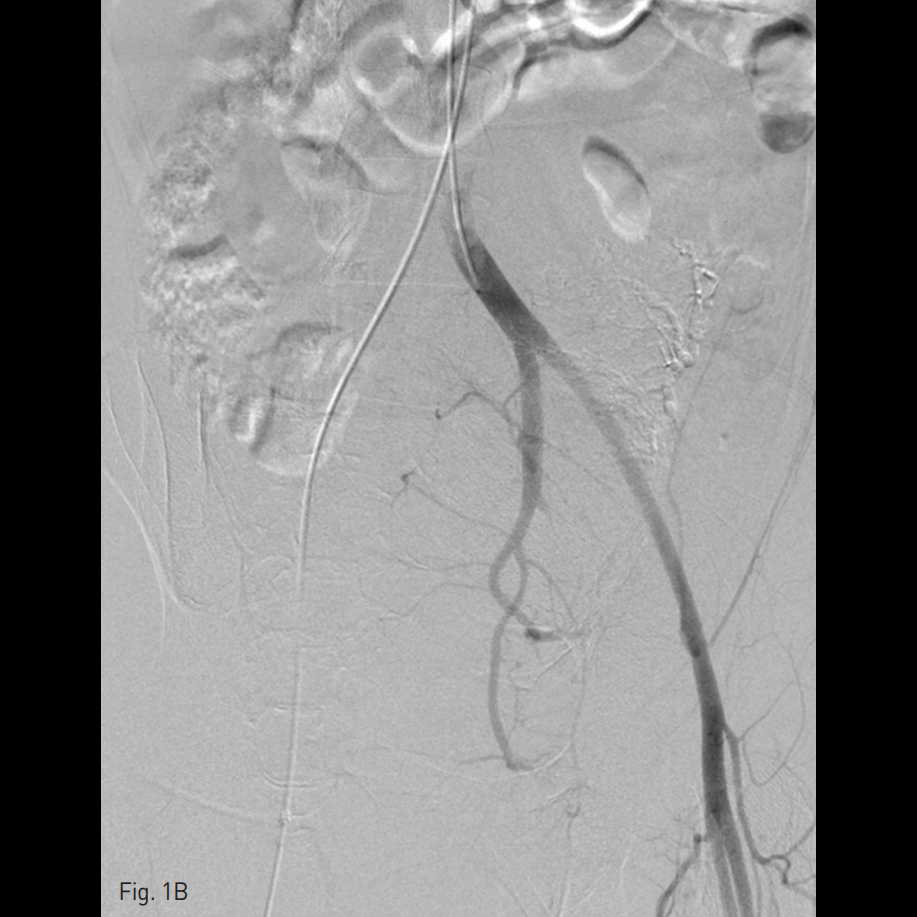

우측 총대퇴동맥을 천자하여 5 Fr sheath를 삽입하고, 5 Fr RUC catheter (Roberts Uterine Catheter, COOK medical, Bloomington, IN, USA)를 이용하여 좌측 내측 장골동맥을 선택하여 조영술을 시행한 뒤 좌측 자궁동맥을 선택하여 조영술 시행하였으며 (Fig. 1A), 출혈의심소견이 있어 gelfoam을 이용하여 색전술을 시행하였다 (Fig. 1B). 이후에 시행한 우측 내측 장골동맥을 선택하여 조영술을 시행한 뒤 (Fig. 1C), 우측 자궁동맥을 초선택하여 조영술을 시행하였을 때, 우측 자궁동맥이 비후되어 있어, gelfoam을 이용하여 색전술을 시행하였다. 색전술 직후 산부인과 진찰에서 지속적인 출혈소견이 보였다. 이에 5 Fr pigtail catheter를 이용하여, 대동맥 조영술을 시행하였다. 하장간막동맥 (Inferior mesenteric artery)으로 부터 출혈 소견이 관찰되었다 (Fig. 2A). 이에 대해서 2.2 Fr 마이크로카테터 (Progreat, Terumo, Japan)를 이용하여 하장간막동맥을 초선택하여 코일(Nester microcoil, COOK Medical, Bloomington, IN, USA)과 gelfoam (Spongostan, Ferrosan Medical Devices, Denmark)을 이용하여 색전술을 시행하였다 (Fig. 2B). 이후 다시 하장간막동맥 조영술을 시행하여 더 이상의 출혈이 없음을 확인하고 시술을 종료하였다 (Fig. 2C).

Fig. 2

A. Aortogram revealed active extravasation of contrast media from the distal branch of the IMA.

B. Active bleeding was better visualized on angiogram using 2Fr microca theter.

C. Bleeding was controlled after coil embolization.